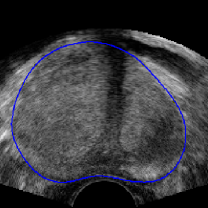

Refer to caption

Figure 7: Intensity shift correlation model. Fig. (a) shows the floating volume, Fig. (d) the fixed volume (after rigid registration), Fig. (b) the elastic registration with the SSD correlation model and Fig. (c) shows the result with the intensity shift correlation model and inverse consistency constraints. All other parameters were identical for both registrations. The SSD driven registration is incorrect because of various local intensity shifts that are caused by the difference in probe pressure between the acquisition of the fixed and the floating images. The intensity shift correlation model correctly handles this problem and converges to the physically correct result.